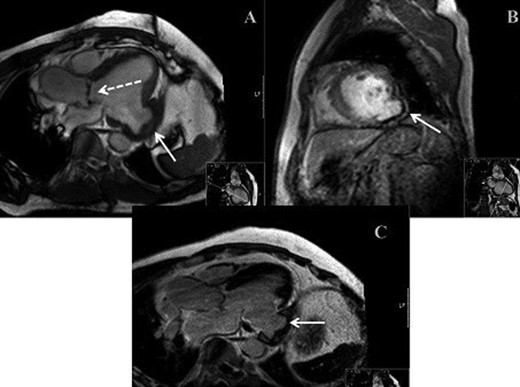

(A) MRI demonstrating bicuspid aortic valve (dashed arrow) and LVA (solid arrow). (B) MRI demonstrating parasagittal view of LVA. (C) MRI demonstrating mid-axial view of LVA.

We report on a 57-year-old gentleman who initially presented with a 6-month history of heavy central chest pain, back and shoulder pain and shortness of breath on exertion (New York Heart Association Classification (NYHA) III, Canadian Cardiovascular Society Angina Classification (CCS) II). He suffered an inferior myocardial infarction in 2007 and has a known bicuspid aortic valve under follow-up. Risk factors for ischaemic heart disease include current smoking and a positive family history of heart disease on his maternal side. On admission, a transoesophageal ECHO (TOE) (Fig. 1) and cardiac magnetic resonance imaging (MRI) (Fig. 2) were carried out and demonstrated the bicuspid aortic valve with a mixed stenosis/regurgitation pattern (moderate–severe) (Fig. 1A). In addition, marked left ventricular dilatation and an inferior LVA extending from the base to the mid-cavity of the left ventricle measuring 4.5 cm across the orifice (Fig. 1B) were seen. The aneurysm was thin walled, with dyskinetic motion with evidence of a dense thrombus adherent to the wall. The inferior wall was noted to be akinetic and non-viable. Preoperative LVEF was 60%. The angiogram showed stenosis of the right coronary artery (Fig. 3B) in the mid-segment together with distal left anterior descending disease (Fig. 3A).